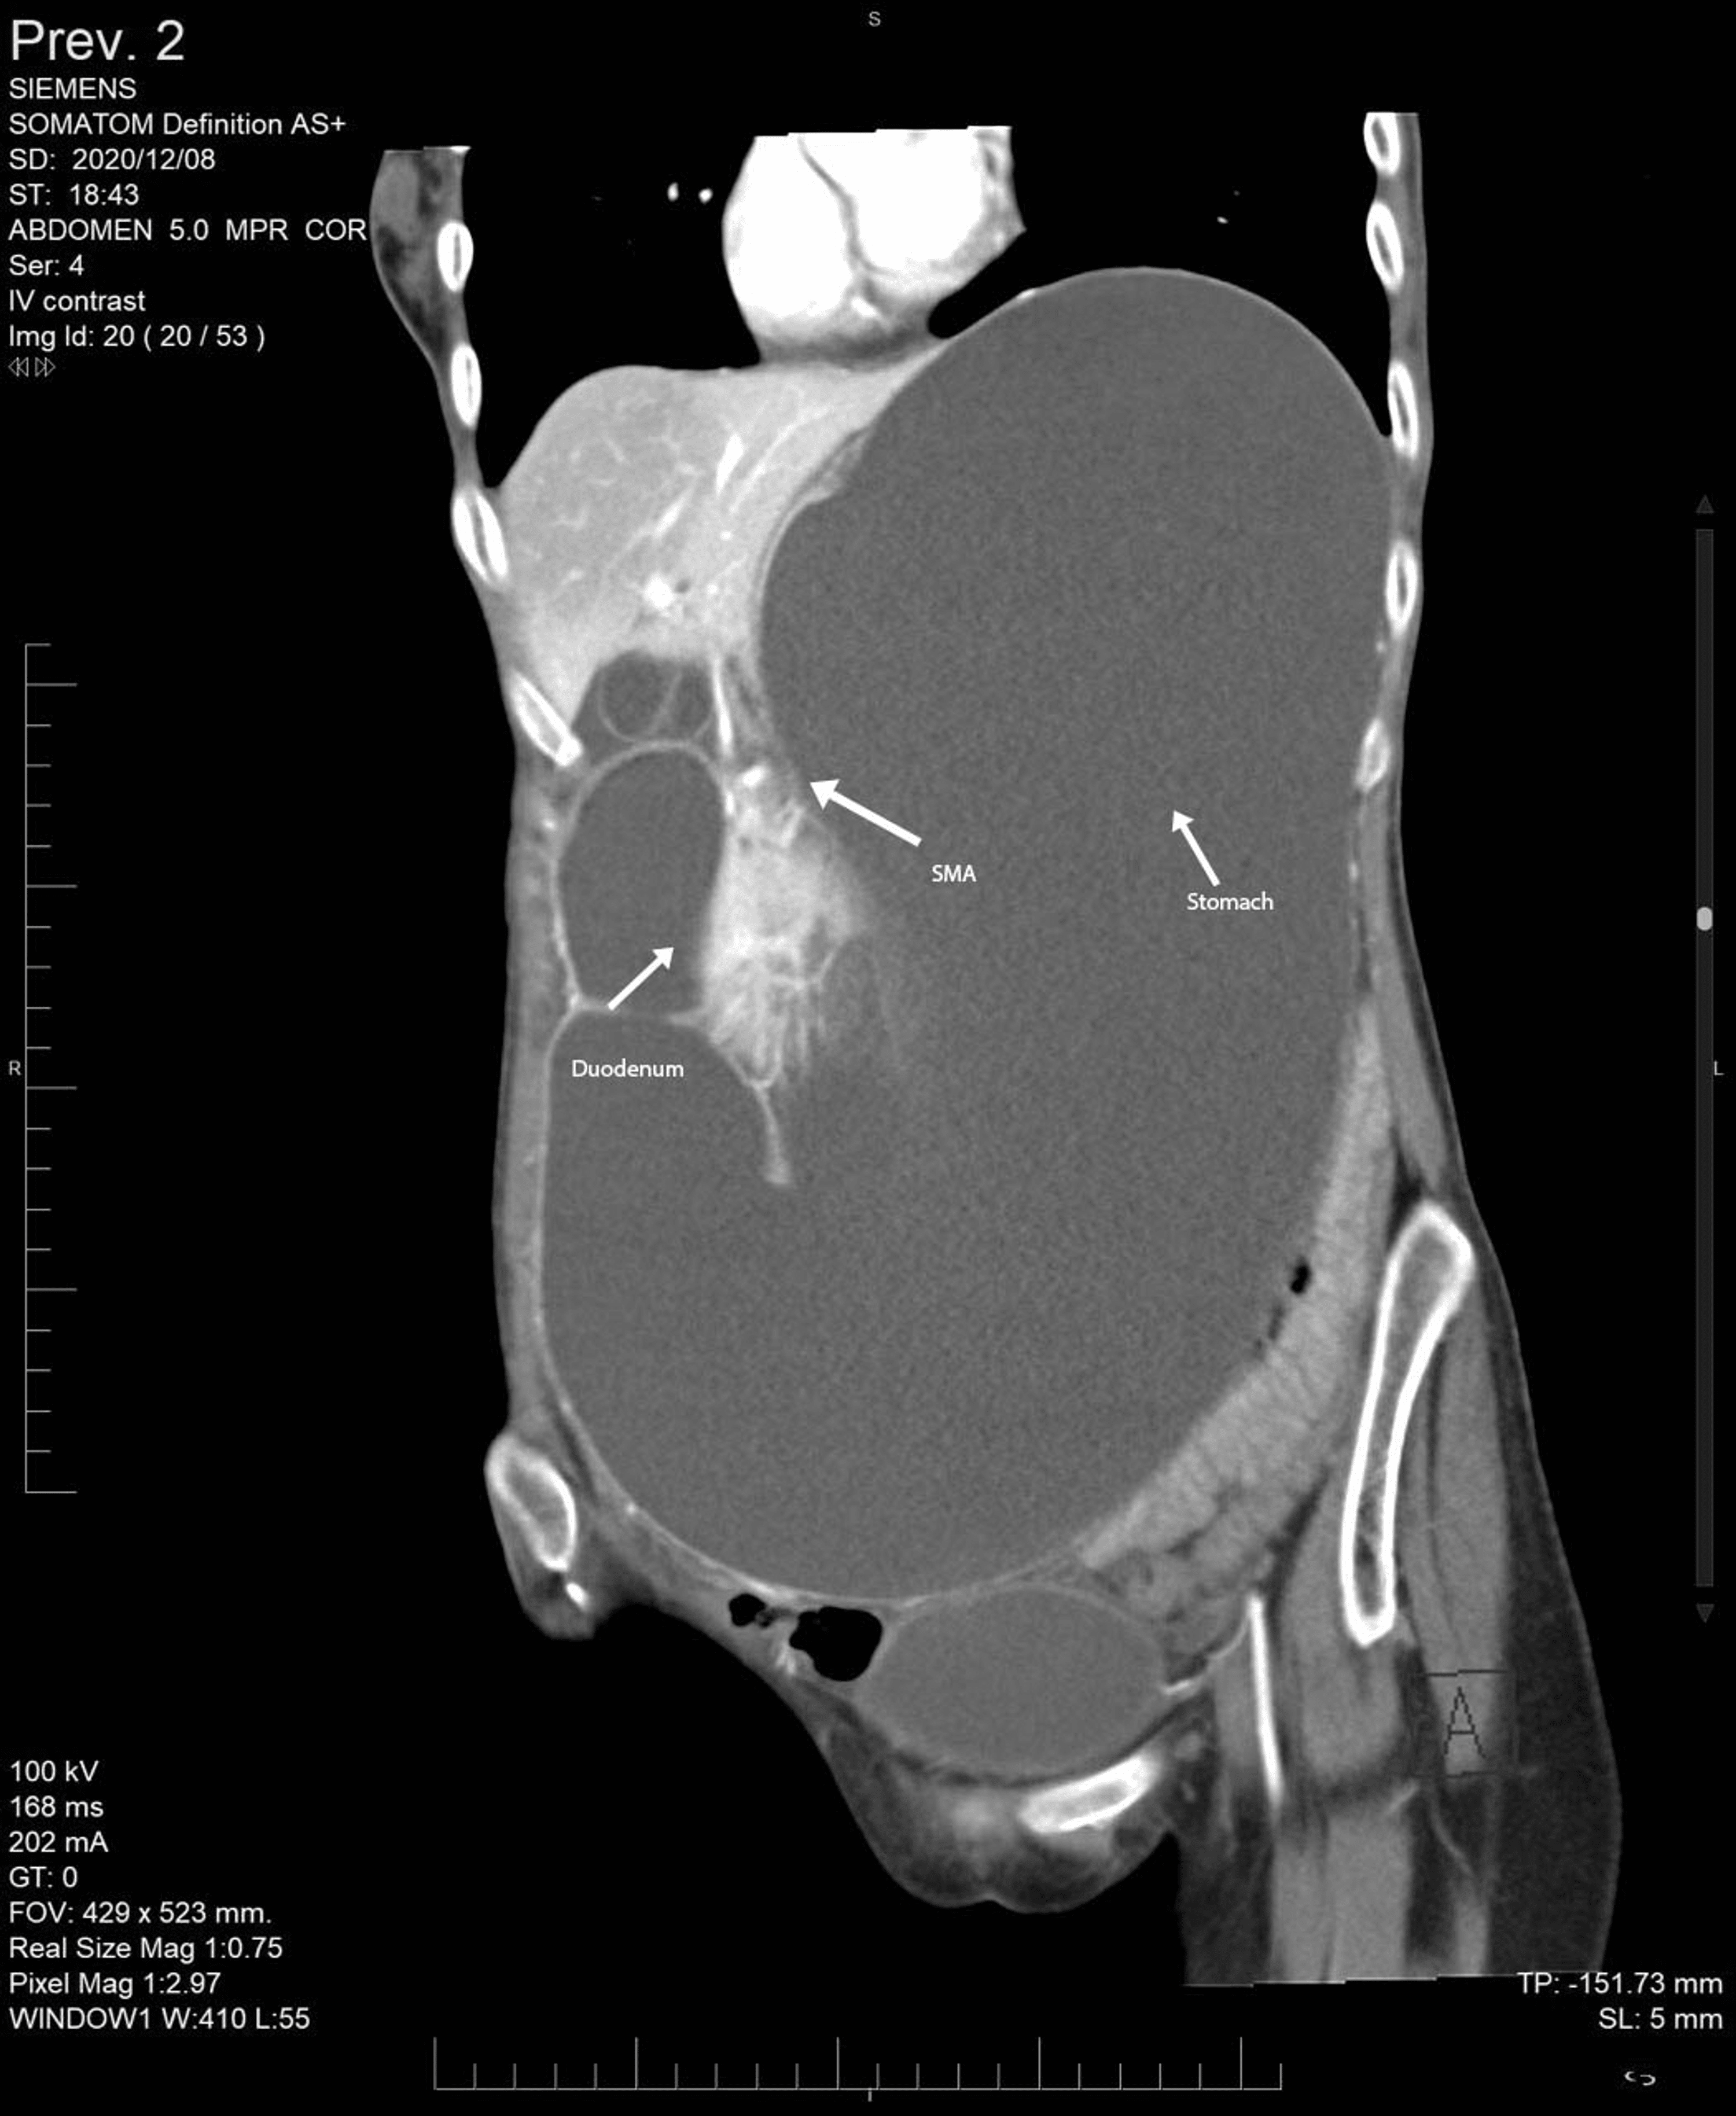

A Rare Presentation of Superior Mesenteric Artery Syndrome as Acute

A Rare Presentation of Superior Mesenteric Artery Syndrome as Acute of Grossly Unremarkable In Medical Terms . Source: www.cureus.com